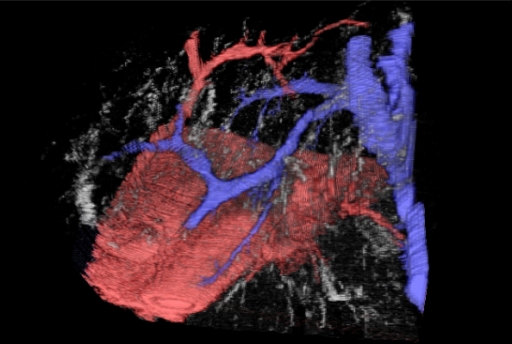

We develop custom advanced algorithms and write our own software to provide truly unique services for cutting edge medical research. Some of our techniques are illustrated above: (Left) Virtual dye casting, (Middle) Metal artefact reduction in CT scans, (Right) 3D printed models derived from a patient's CT imaging. Some details are given below:

- 3D Serial Tissue Section Reconstruction - We have over 20 years experience in making high resolution 3D computer models of complex tissue and intracellular microanatomy from serial sections. These sections may be physical histology sections or optical sections using optical sectioning microscopy and 3D deconvolution. We are one of the few centres that can offer 3D deconvolution on bright field microscopy (as opposed to the simpler problem of fluorescence imaging). However, we don't stop at just making the 3D model. We have also developed unique visualisation tools and functional methods such as virtual dye casting. This allows complex microvascular and other connected structures to be traced in 3D in a computer model - without the need to make a physical model or inject the actual tissue (which would be impossible at this microscopic scale anyway). The figure at the top of this page on the left and, in greater detail, the figure below give an example of such dye casting done on liver histology showing the microvascular relationships in the human liver acinus. These are just static shots from a fully interactive virtual 3D model. This was published as: Tadrous, P. J., A. Hall, and A. P. Dhillon. "Advances in multiresolution serial section 3d reconstruction: applications to liver microarchitecutre." The Journal of Pathology 220 (2010): S11.